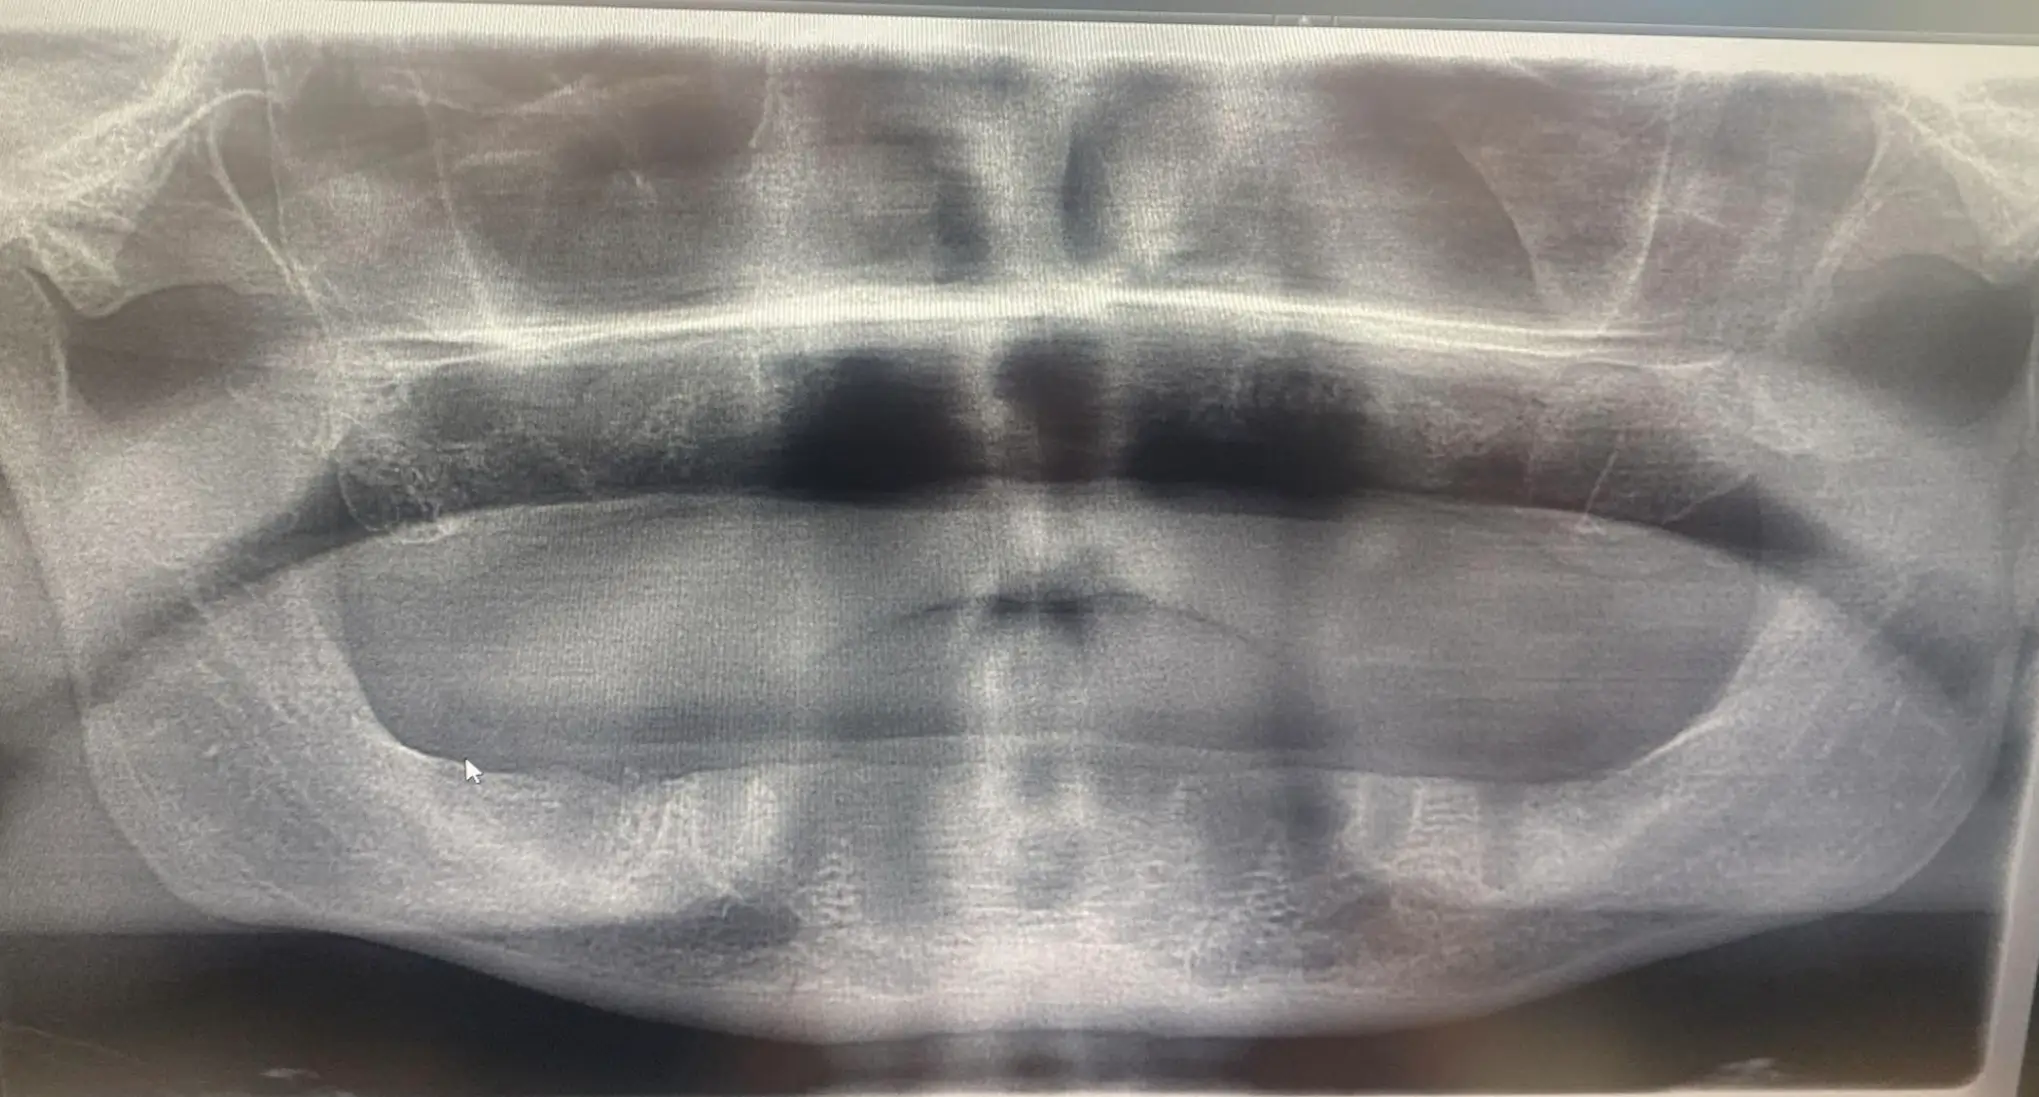

The GoFundMe goes on to say that UK dentists have since informed Jon that he ‘did not have sufficient bone to support the implants’ and that he has ‘no ridge, so dentures are not suitable for him’.